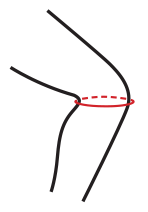

TABELA ROZMIAROWA

| Rozmiar | Obwód kolana | Odpowiedni dla wieku | Sposób dokonywania pomiaru |

|---|---|---|---|

| 1 | 23 – 27 cm | 2 – 5 lat |  |

| 2 | 27 – 34 cm | 4 – 12 lat |